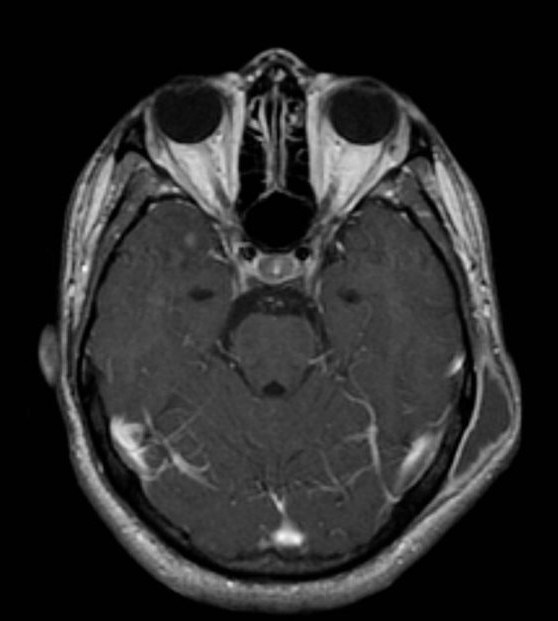

Внелегочный туберкулез мозговых оболочек считается наиболее тяжелой формой заболевания. Недуг развивается стремительно и при отсутствии лечения ведет к необратимым нарушениям в работе нервной системы, а иногда и к смерти. Правда, на сегодняшний день случаи данного заболевания регистрируются редко.

В свое время наиболее часто диагностировался подобный внелегочный туберкулез у детей. Уменьшение распространения недуга связывают с массовым проведением прививки БЦЖ среди новорожденных. Это теория подтверждает фактом, что на сегодняшний день туберкулезный менингит регистрируется среди детей без вакцинации.

Краткосрочные приступы головной боли, незначительное повышение температуры, слабость и общее недомогание — именно так начинается внелегочный туберкулез. Симптомы появляются по мере развития менингита. Головная боль появляется чаще и становится более интенсивной. Температура тела поднимается до 39-40 градусов. Повышается возбудимость, развивается чувствительность к свету. Характерным признаком является появление анорексии и резкая потеря веса. При отсутствии лечения на 3-5 неделе наступает смерть пациента, которая связана с параличом дыхательного или сосудодвигательного центра головного мозга.

Туберкулезный менингит

Заболевание возникает, когда микобактерии туберкулёза, распространяясь, добираются до мозга, что влечет за собой воспалительные процессы.

Возрастной дифференциал по данному заболеванию указывает на то, что у детей шанс заразиться намного выше, чем у взрослых. Впрочем, та же ситуация обстоит и с обыкновенным менингитом.

Периоды развития туберкулёзного менингита различны.

Продромальный – последовательное (до 56 дней) развитие:

- Тошнота.

- Лихорадка.

- Головная боль.

- Головокружение.

- Температура.

- Задержка стула и мочи.

- Раздражения – через 7-15 дней после первого периода:

- Появление менингеального синдрома в течение недели после начала второго периода.

- Также может наблюдаться снижение зрения, косоглазие, различие в диаметре зрачков, паралич века глухота.

- Могут наблюдаться потеря речи и слабость в конечностях.

- Потери сознания.

Терминальный – от 2 до 3,5 недель:

- Парезы.

- Параличи.

- Потеря сознания.

- Тахикардия.

- Высокая температура (около 40С).

- Пролежни.

После проведение пункции, исследуют цереброспинальную жидкость больного. Это должно показать:

- Плеоцитоз;

- преобладание лимфоцитов;

- повышение содержания белка;

- увеличение глобулинов.

- Биохимическое исследование покажет снижение уровня глюкозы. Используется компьютерная и магниторезонансная томография.

Срочная госпитализация больного для дальнейшего исследования симптомов и установления точного диагноза. Болезнь относиться к летальным, поэтому отсутствие должного лечение приведет к смерти пациента.